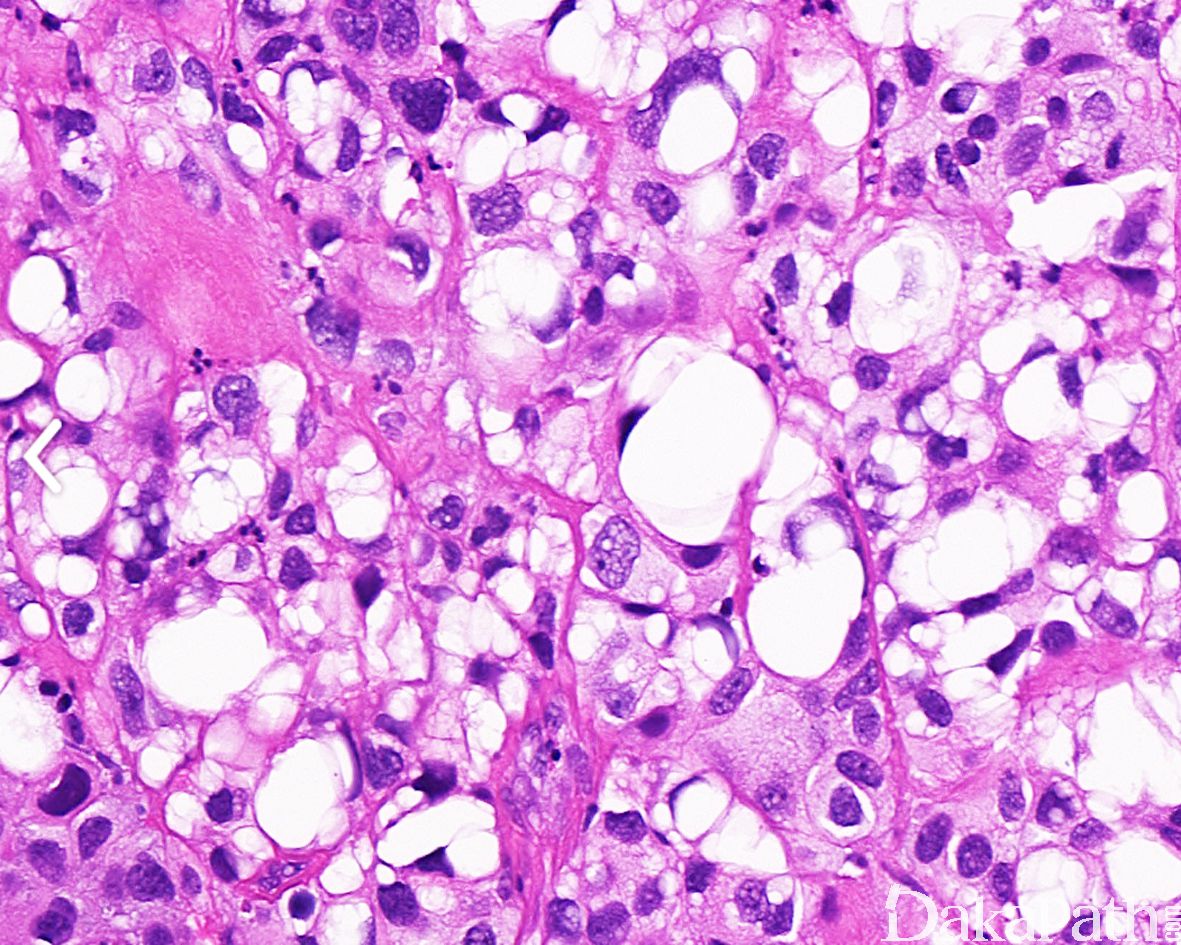

浸润性尿路上皮癌,富脂质

Infiltrating urothelial carcinoma, Lipid-rich

尿路上皮癌瘤细胞胞浆内存在多个空泡挤压核形成类似于脂肪母细胞的瘤细胞

特征性形态学改变是存在大的脂肪母细胞样细胞,具有 1 个或多个胞浆空泡,挤压细胞核;

常和其它类型或普通型尿路上皮癌混合存在,脂质细胞通常占肿瘤成分的 10%-50%,